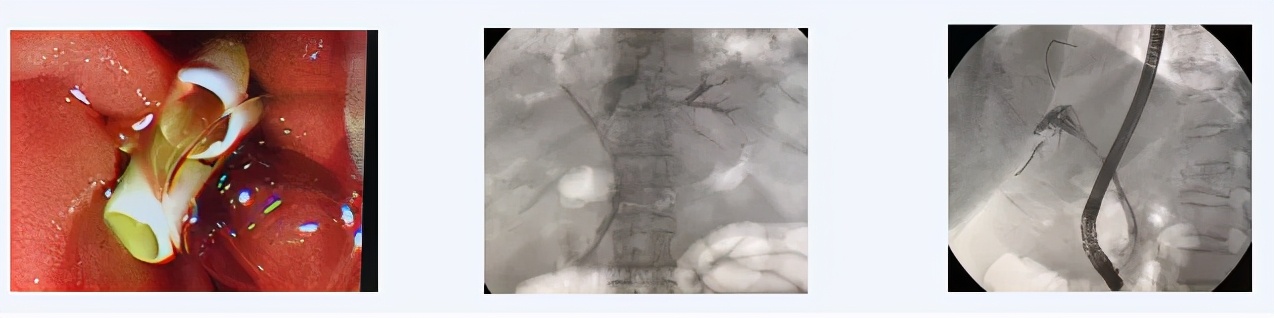

患者89岁,男性,因“梗阻性黄疸,肝门部胆管占位,胆总管狭窄”由老年病科转至西青医院普通外科病区完善相关检查,考虑肝门部恶性肿瘤。主治医师王金伟主持病例讨论中提到,考虑到患者高龄,基础疾病较多,无法耐受手术治疗,而患者如无法解除梗阻状态,病情可能进一步发展并危及生命。在权衡患者情况后,通过与患者及家属沟通,选择ERCP进行针对性微创化治疗方案。遂后,在天津市南开医院内镜专家的指导下,王金伟医生联合内镜室护理团队在介入室局麻下,通过十二指肠镜成功为该高龄患者放置两根胆道支架达左右肝管引流肿瘤上段胆汁改善肝功能,这将为延续患者生命发挥重要作用,患者术后好转出院。

患者75岁,女性,患者因“胆总管结石,胆道感染,急性胆囊炎,胆囊结石”急症收治西青医院,既往右肾恶性肿瘤史,全身多处转移,腹腔内多发转移,同时合并心脏支架术后,肾功能不全等情况。主治医师胡石甫结合患者肿瘤晚期病史,无法耐受手术情况,建议患者首选ERCP解除胆道梗阻,进行缓解症状治疗。通过抗炎对症治疗后,在天津市南开医院内镜专家的指导下,王金伟医生再次与内镜室护理团队协作在介入室局麻下通过十二指肠镜成功为该患者放置胆道支架改善梗阻,遂后患者病情恢复良好,日前已好转出院。

经内镜逆行胰胆管造影(ERCP)是指将十二指肠镜插至十二指肠乳头,由内镜活检管道插入造影导管至胆管或胰管,经造影导管注射造影剂作X 线胰胆管造影。此操作主要适用于1、疑有胆总管结石、肿瘤、炎症或梗阻性黄疸原因不明者;2、胆囊切除术后或胆总管术后胆系症状复发;3、怀疑胰腺肿瘤、慢性胰腺炎或复发性胰腺炎缓解期;4、十二指肠乳头或壶腹部肿瘤;5、原因不明上腹痛,怀疑胆胰疾病;6、其他胆系疾病需行内镜下治疗者。